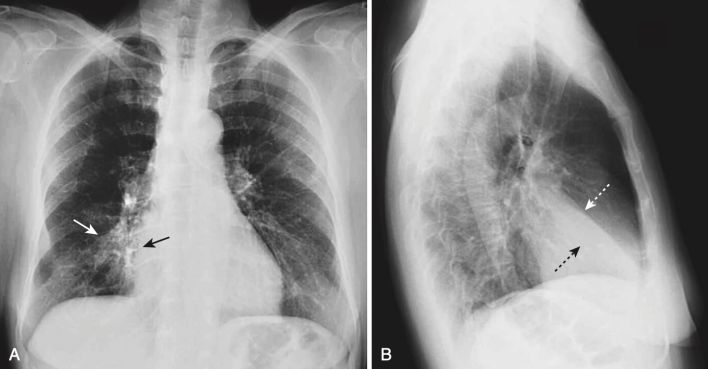

Xẹp phổi thùy giữa bên phải (xem Hình 1)

- Trên X quang thẳng:

- Có một đậm độ hình tam giác với đáy phủ bóng bờ với bờ tim phải và đỉnh của nó hướng về thành ngực bên.

- Rãnh liên thùy bé bị dịch chuyển xuống dưới.

- Trên phim X quang nghiêng:

- Có đậm độ hình tam giác với đáy hướng ra phía trước và đỉnh ở rốn phổi.

- Rãnh liên thùy bé có thể bị dịch chuyển xuống dưới và rãnh liên thùy lớn lên trên.